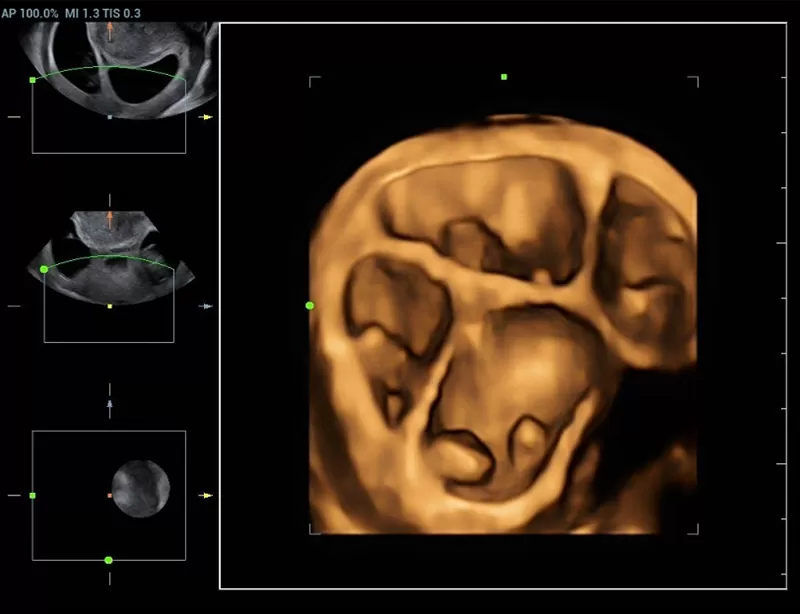

Στη διάθεση σας θα βρίσκονται καταρτισμένοι συνεργάτες μας οι οποίοι θα αναλάβουν να σας παρουσιάσουν τις δυνατότητες του Premium υπερηχογράφου Resona που αποτελεί μια πραγματικά επαναστατική πλατφόρμα, με δεκαπλάσια ταχύτητα σάρωσης χάρις στη μοναδική τεχνολογία zone sonography technology ZST+ που διαθέτει.

Η σειρά Resona ξεχωρίζει όχι μόνο για την κορυφαία απεικονιστική της τεχνολογία αλλά και για τα ευέλικτα εργαλεία ανάλυσης, προσφέροντας ποιότητα απεικόνισης υψηλού επιπέδου και αυξημένη διαγνωστική ακρίβεια.

Οι καινοτόμες τεχνολογίες:

- New iLive with Hyaline

καθιστούν τη σειρά Resona μια από τις πιο ισχυρές διαγνωστικές πλατφόρμες που υπάρχουν σήμερα στην υπηρεσία της Ιατρικής.